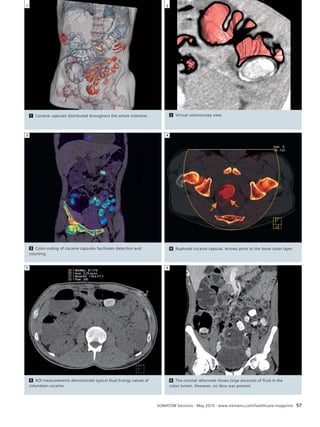

1

L R

3 Conventional angiography

demonstrates the right MCA

aneurysm in the right internal

carotid artery injection (ar-row).

SOMATOM Sessions · May 2010 · www.siemens.com/healthcare-magazine 53

4

2 Head CT without contrast

demonstrates right sylvian

fissure and interhemispheric

fissure hyperdensity consis-tent

with subarachnoid hem-orrhage

(arrows). The tempo-ral

horns are mildly dilated

due to early obstructing

hydrocephalus (arrowhead).

2 3

Neurology Clinical Results

4 VPCT axial multi-parameter view showing a Maximum Intensity Projection (MIP), Cerebral Blood Flow (CBF), Cerebral Blood Volume (CBV), Time To Peak,

Time To Drain (TTD) and Mean Transit Time (MTT), MTT and TTD (time to drain, a Siemens origin parameter) being the most useful parameters in this case.

Clinical Results Neurology

5 3D view of the Time To Drain (TTD) parameter map of the entire brain. Time to drain is a Siemens unique deconvolution based parameter de-scribing

the time of the earliest washout of contrast medium in seconds. It is a very sensitve parameter to detect perfusion asymetries like MTT.